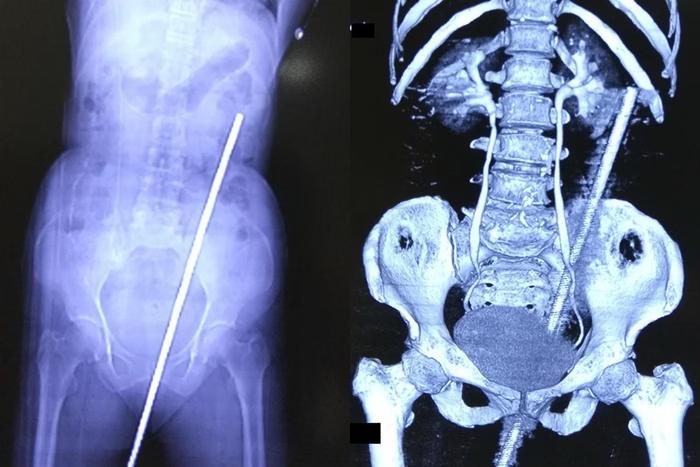

Mulher fica empalada em ferro de 60 cm após cair em pastoFoto mostra barra de ferro de 60 cm que foi retirada do corpo da mulher Foto: International Journal of Surgery Case Reports

Uma mulher indiana de 65 anos escapou da morte após de ter sido empalada por uma barra de metal enferrujada de quase 60 centímetros. O acidente aconteceu quando ela escorregou no campo e caiu exatamente em cima do artefato, que estava parcialmente enterrado no solo. O caso foi publicado no International Journal of Surgery Case Reports.

Mulher fica empalada em ferro de 60 cm após cair em pastoBarra de ferro de 60 cm que foi retirada do corpo da mulher Foto: International Journal of Surgery Case Reports

O objeto entrou pelo reto da mulher, causando uma perfuração que se estendeu até as costas. Milagrosamente, não houve danos aos vasos sanguíneos ou órgãos vitais, segundo o relatório médico.

A mulher recebeu antibióticos e uma vacina contra tétano para prevenir infecções, pois a barra de metal estava enferrujada e coberta de lama e esterco de vaca. Em seguida, foi submetida a uma cirurgia de duas horas para a remoção da barra.